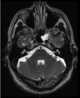

Meningoencephalocele

Encephalocele is a neural tube defect characterized by sac-like protrusions of the brain and the membranes that cover it through openings in the skull. These defects are caused by failure of the neural tube to close completely during fetal development. [Source: Wikipedia ]